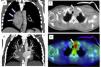

La enfermedad de Castleman no es una única enfermedad. Bajo este epónimo se reúne un heterogéneo grupo de trastornos linfoproliferativos no clonales, muy infrecuentes, con un amplio espectro de expresión clínica. Se han descrito 3 tipos histológicos, junto con varias formas clínicas, según la forma de presentación, el sustrato histológico y las enfermedades asociadas. La interleucina 6, los polimorfismos del receptor de esta interleucina, el virus de la inmunodeficiencia humana y el virus herpes humano tipo 8 están implicados en la etiopatogenia y su estudio ha aportado luz al conocimiento de un síndrome cuya incidencia es desconocida. A pesar de avances recientes e importantes en su conocimiento y de la progresiva experiencia terapéutica con rituximab, tocilizumab y siltuximab, aún existen preguntas difíciles de contestar con los factores etiológicos, el abordaje terapéutico óptimo y el pronóstico.

Castleman's disease is not just a single disease but rather an uncommon, heterogeneous group of nonclonal lymphoproliferative disorders, which have a broad spectrum of clinical expression. Three histological types have been reported, along with several clinical forms according to clinical presentation, histological substrate and associated diseases. Interleukin-6, its receptor polymorphisms, the human immunodeficiency virus and the human herpes virus 8 are involved in the etiopathogenesis of Castleman's disease. The study of this disease has shed light on a syndrome whose incidence is unknown. Despite recent significant advances in our understanding of this disease and the increasing therapeutic experience with rituximab, tocilizumab and siltuximab, there are still difficult questions concerning its aetiology, prognosis and optimal treatment.